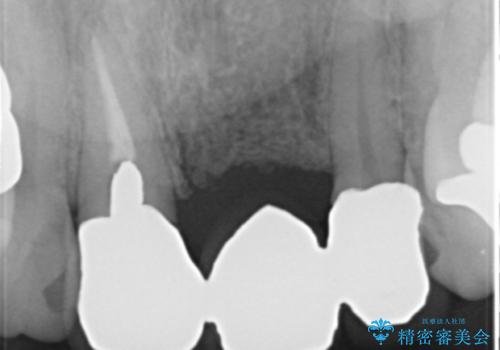

前歯のレジン前装冠(保険内)によるブリッジは、金属で裏打ちされており透明感がなく不自然で、ポンティックも必要以上に長く作られていました。

古いブリッジと金属の土台を除去し、ファイバーコア(金属を使わない強くてしなやかな土台)を植立したのち、オールセラミックのブリッジによる補綴治療を行いました。。